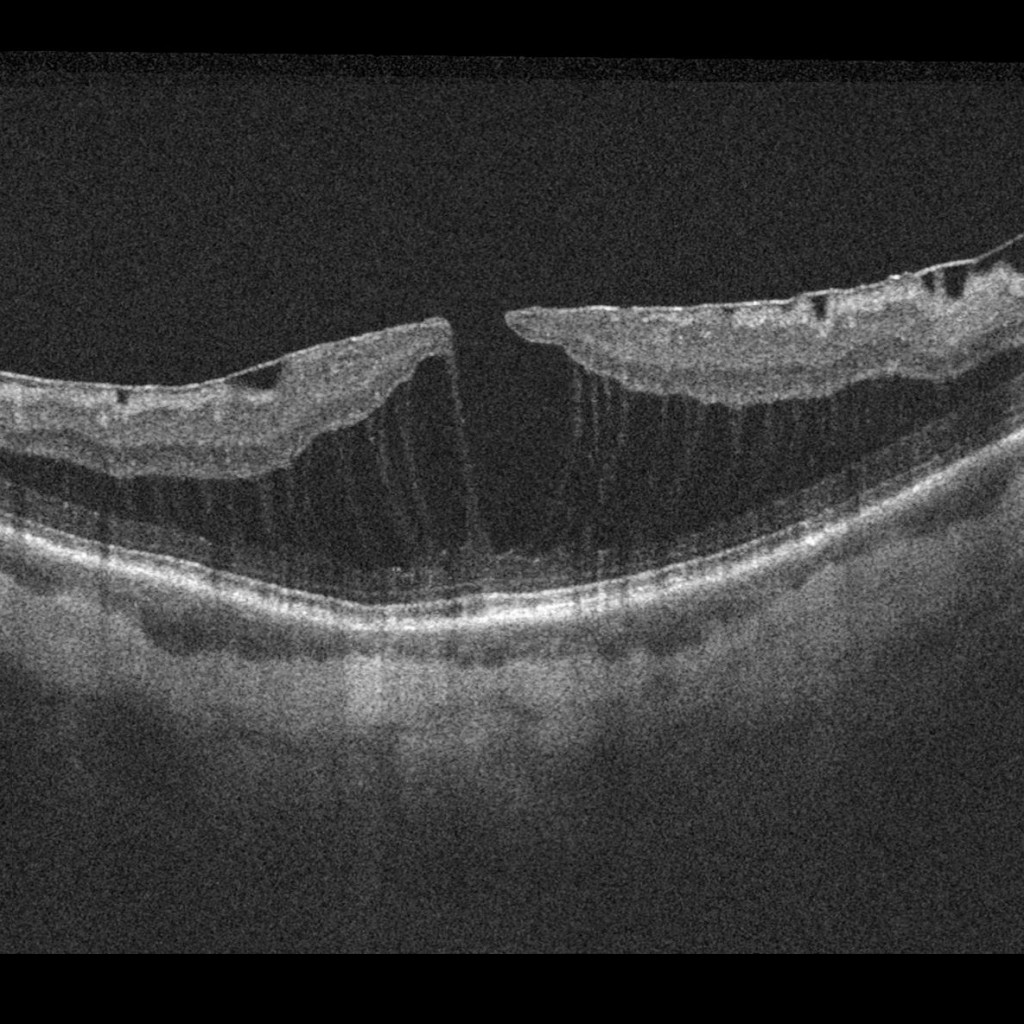

• Myopic Maculoschisis

maculoschisis_edited

Full size 1185 × 1185

Published inmaculoschisis_edited